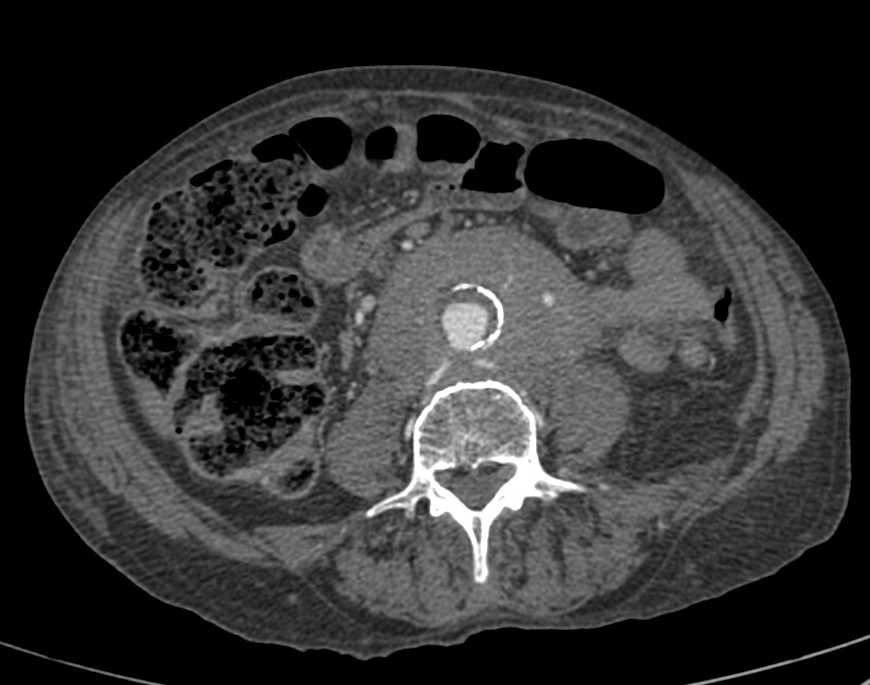

Paciente con aneurisma de aorta con dolor abdominal difuso y bilateral. Sin otros hallazgos clínicos y ni analíticos. Constantes vitales estables.

El TC abdominal en fase portal y excretora evidencian una masa que compromete ambos uréteres, más acentuada a la izquierda, produce hidronefrosis bilateral, hallazgo muy infrecuente en el linfoma. Además es isodenso con respecto al músculo, rodea la aorta por la parte anterior, no la desplaza hacia adelante y está en situación infrarrenal predominantemente. No hay adenopatías. Solución: estamos ante una Fibrosis Retroperitoneal.